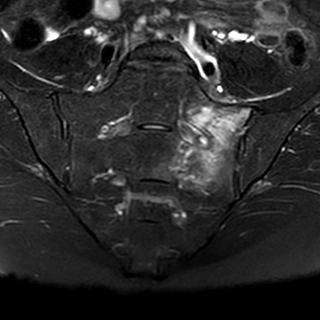

Hoại tử vô mạch chỏm xương đùi (Osteonecrosis of the femoral head)